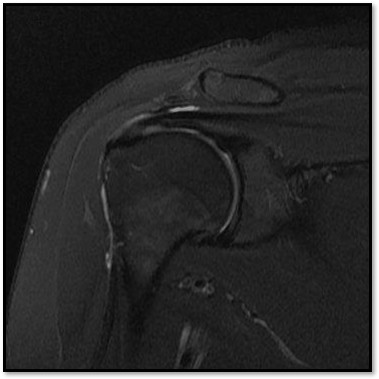

MRI와 초음파를 다시 검토했습니다.

회전근개 극상건의 관절면측(articular-side) 부분파열.